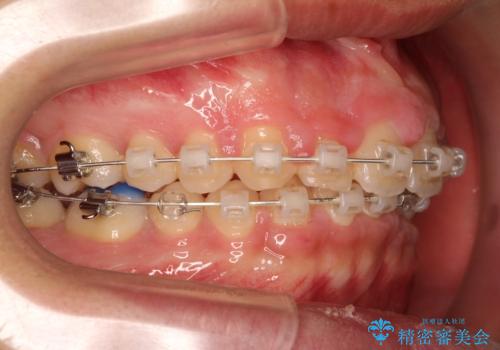

- 矯正装置

- 審美装置(ブラケット:白/ワイヤー:白) アドバンシンク

また、成長期終盤の男の子だったため成長の余力(下顎を前に牽引んし成長を促進する)を期待しアドバンシンクという装置を使い、下顎の骨の成長を利用した矯正治療を行いました。